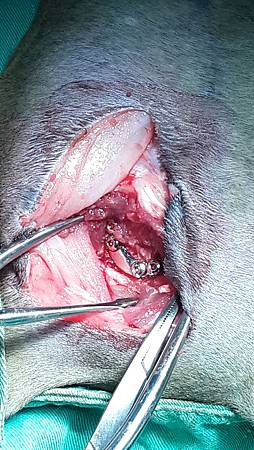

2014-12-22 15.44.21.jpg

骨折修復